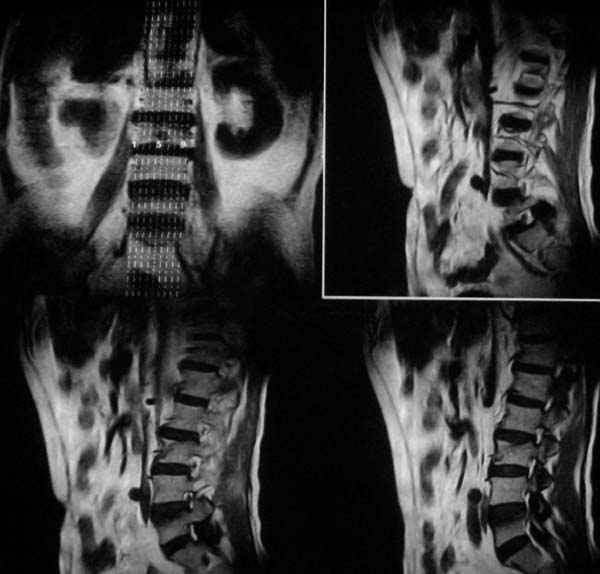

病史特点:

1.中年男性

2.腰疼,双下肢麻木1月。

3.ct 可右肾上腺占位,腰1椎体及附件可见骨质破坏及软组织肿块。

4.mri:腰1椎体及附件t1wi低信号,t2wi高信号。

考虑右侧肾上腺癌骨转移.或右肾上腺及骨均为转移瘤。